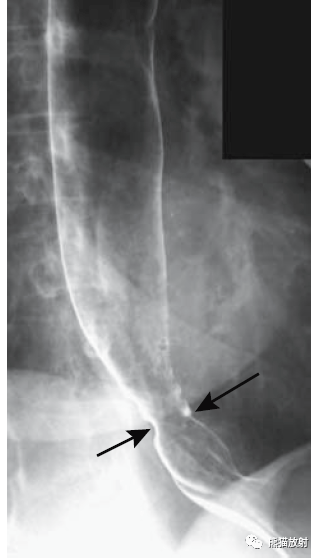

x线钡餐检查:直接征象:膈上疝囊,疝囊内有胃黏膜皱襞影,出现食管胃环.